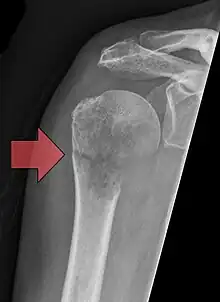

Pathological fracture of the humerus in a patient with metastasis of renal cell carcinoma

A pathologic fracture is a bone fracture caused by weakness of the bone structure that leads to decrease mechanical resistance to normal mechanical loads.[1] This process is most commonly due to osteoporosis, but may also be due to other pathologies such as cancer, infection (such as osteomyelitis), inherited bone disorders, or a bone cyst. Only a small number of conditions are commonly responsible for pathological fractures, including osteoporosis, osteomalacia, Paget's disease, Osteitis, osteogenesis imperfecta, benign bone tumours and cysts, secondary malignant bone tumours and primary malignant bone tumours.

Pathological fractures present as a chalkstick fracture in long bones, and appear as a transverse fractures nearly 90 degrees to the long axis of the bone. In a pathological compression fracture of a spinal vertebra fractures will commonly appear to collapse the entire body of vertebra.